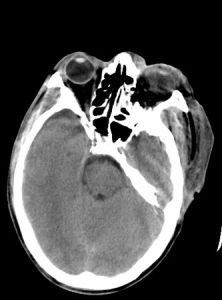

這包括腦血管疾病(如腦出血、腦梗死等)、腦外傷、腦腫瘤、腦炎、中毒性腦病等;

腦電圖、CT可以做出相應的診斷。鑑別